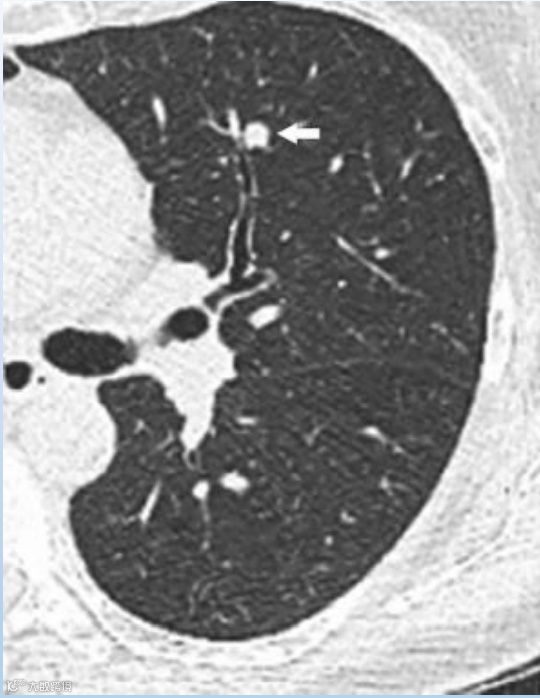

根据美国放射学会(American College of Radiology,ACR)发布的肺部 CT 筛查报告和数据系统(lung imaging reporting and data system, Lung-RADS)1.1版,肺结节可以分为以下几类:

1(阴性):

无结节和确定为良性的肺结节(含良性钙化或脂肪)。

恶性概率:小于1%

2(良性表现或良性生物学行为):

大小或直径无增长,发展为临床侵袭性肺癌的可能性低。

3(良性可能性大):

短期随访可能为良性的结节,包括侵袭性肺癌可能性低的结节。

恶性概率:1-2%

4(可疑恶性):

附加的诊断实验和/或组织标本提示。

4A:恶性概率:5~15%

4B:恶性概率:大于15%